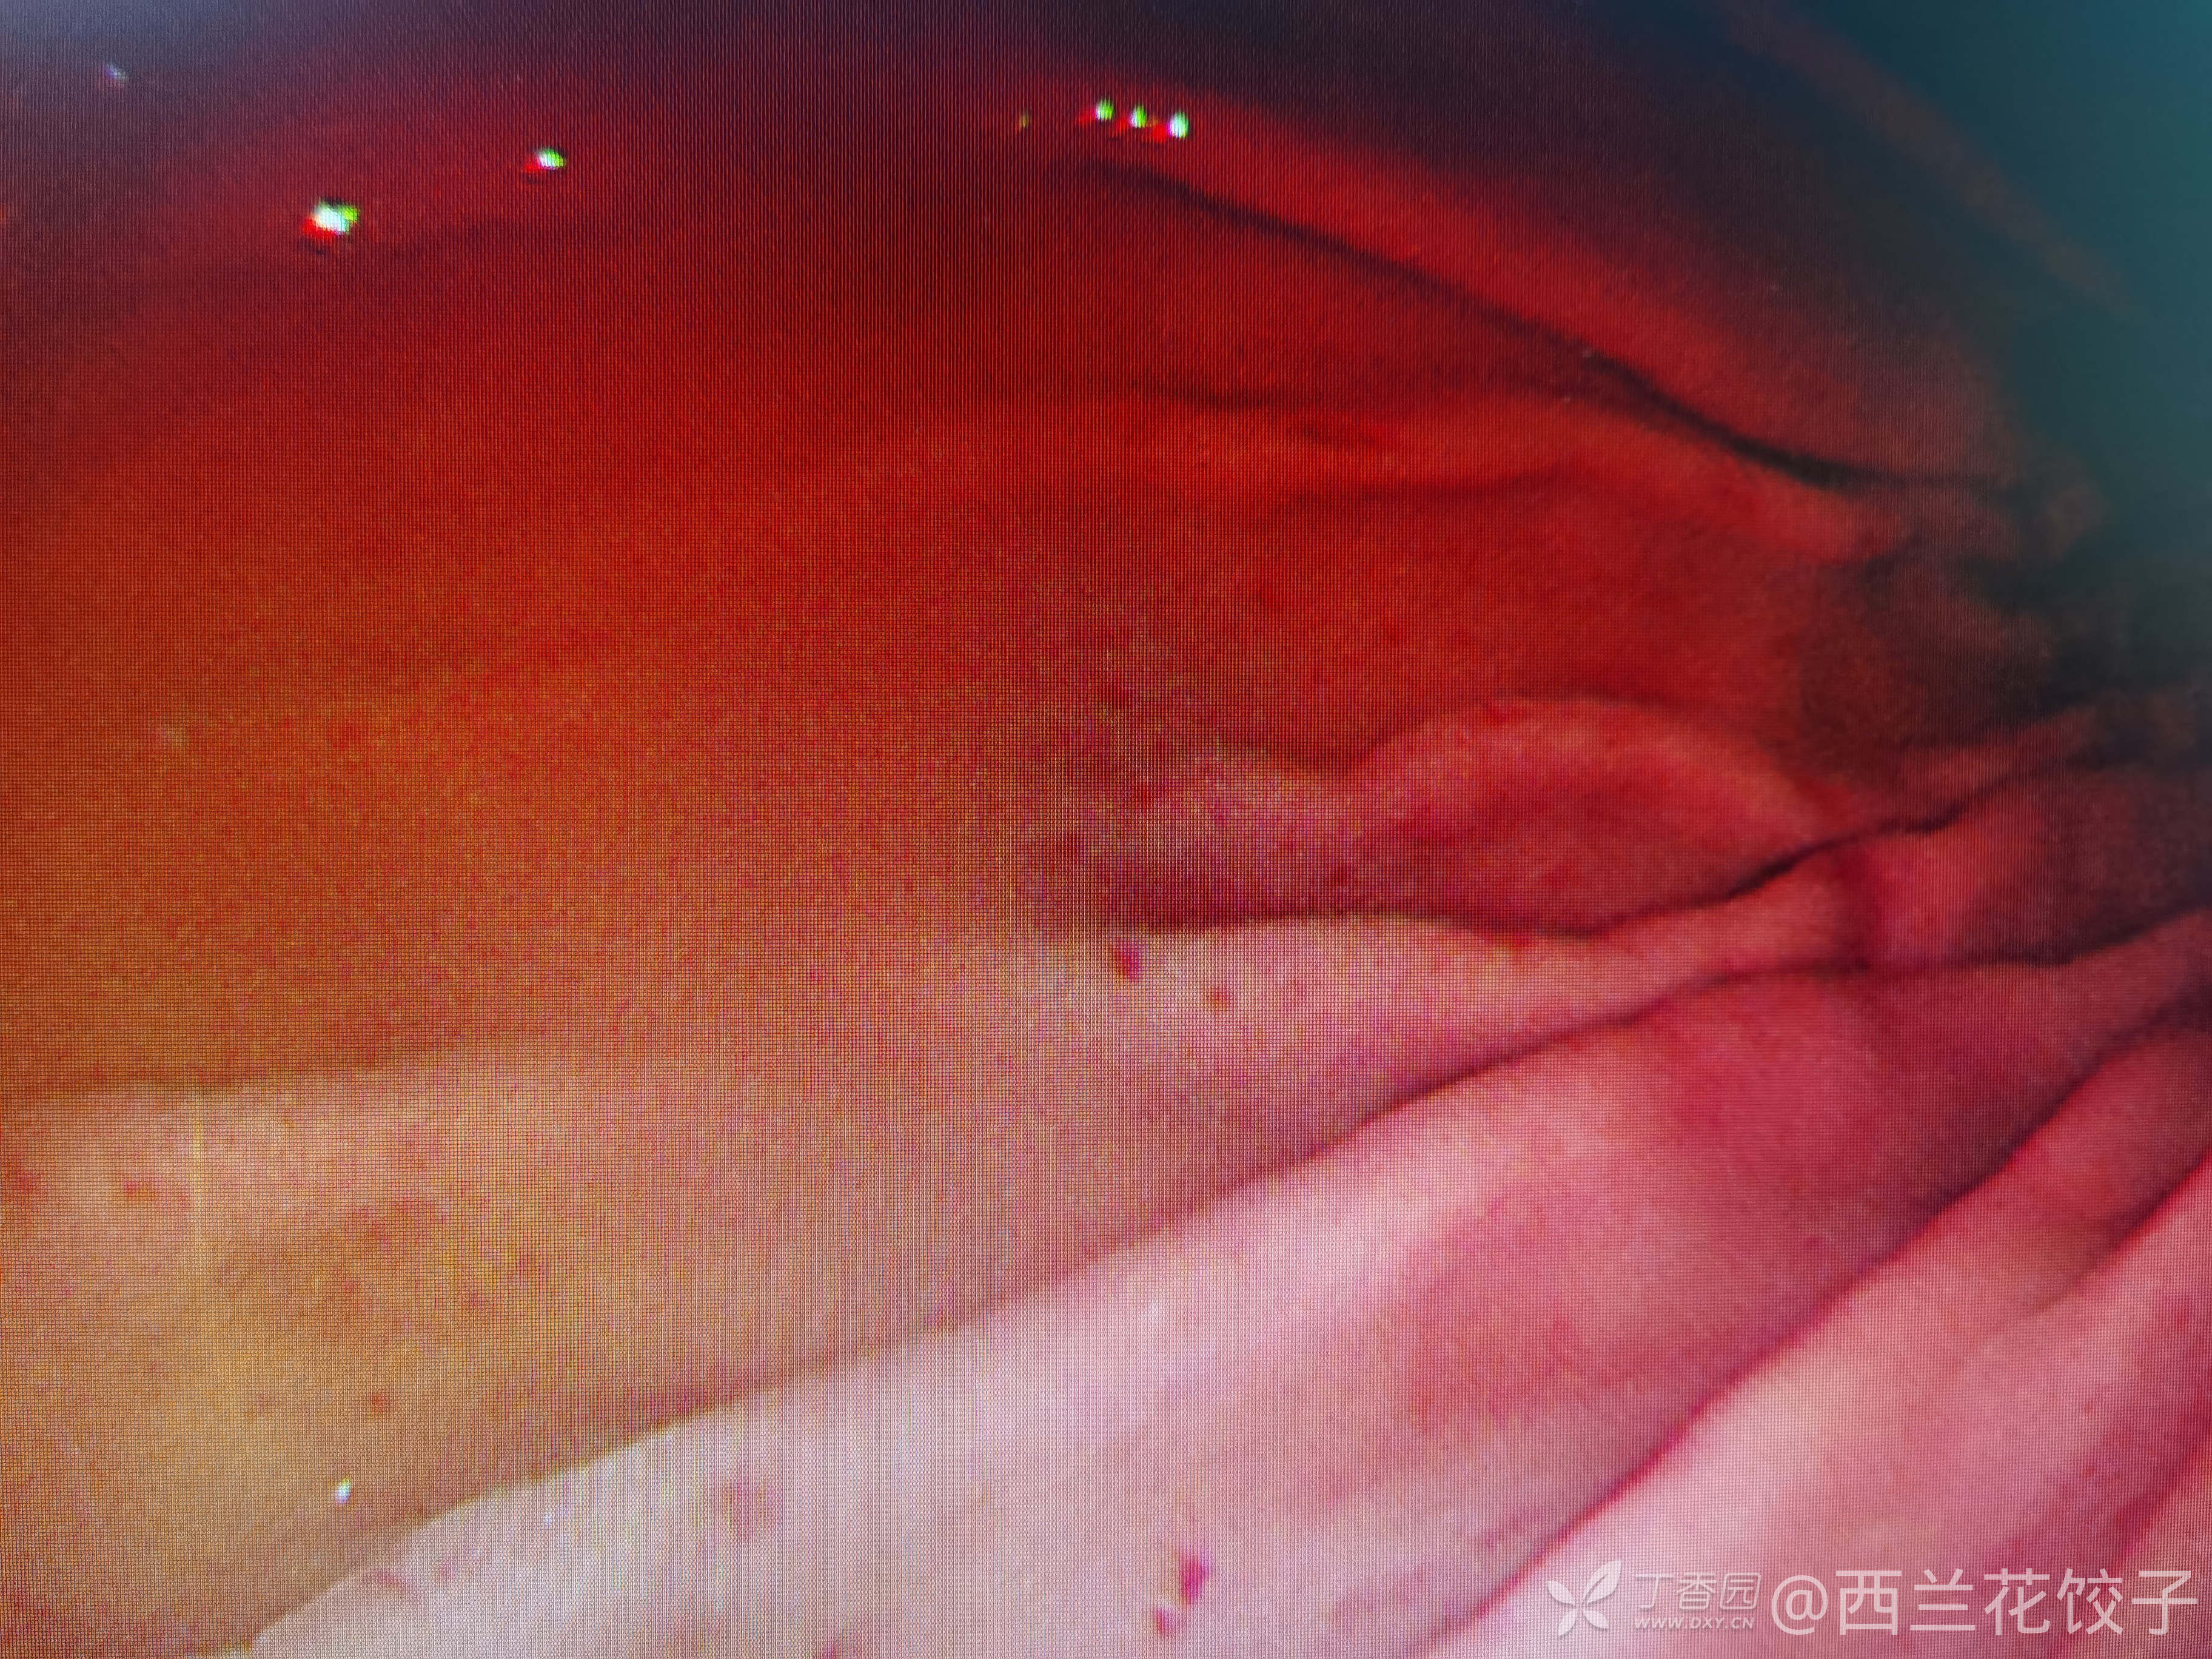

主诉:进行性吞咽困难伴反食3年余,加重1月

简要病史:患者3年来无明显诱因出现吞咽困难,进行性加重,近1月来,基本不能进食饮水,自服奥美拉唑,莫沙必利无好转,遂来我院门诊。

辅助检查:胃镜检查如下,食管内可见大量食物残渣及液体,胃腔内未见明显异常,胸腹部Ct如下,新冠核酸阴性。